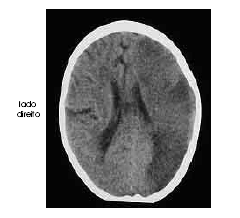

Um homem com 67 anos de idade, lavrador, deu entrada no pronto-socorro após ter sido encontrado, em sua casa, no chão e com dificuldade para falar e deambular. O paciente morava sozinho e os parentes não sabiam informar sobre uso de medicações ou patologias pregressas. Na avaliação, o neurologista identificou afasia mista, hemianopsia homônima direita e hemiparesia direita de predomínio braquifacial. Apesar de apresentar sonolência, o paciente ficava alerta ao chamado. A pressão arterial era de 180 mmHg × 90 mmHg. Foram solicitados exames complementares e de imagem, dos quais uma das imagens é reproduzida abaixo.